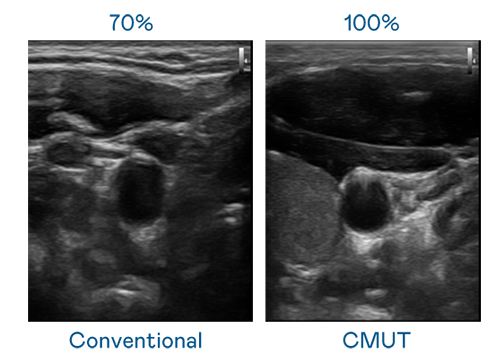

CMUT 技术是一种用电容式微机电元件来产生超音波讯号的技术。与传统 PZT 压电式技术相比,CMUT 频宽增加 30%,更宽频的超音波讯号让影像解析度大幅提升,是实现高影像品质医疗超音波扫描、促进精准医疗发展的关键技术。

大频宽带来超清晰影像

超音波影像的解析度高低,首先取决于探头能发出的讯号频宽。77779193永利 CMUT 可提供高清晰的超音波讯号,提供高频宽、高灵敏度、影像纹理细节更高的超音波影像,协助医护人员缩短影像判读时间及利用精准的医疗影像进行诊断。